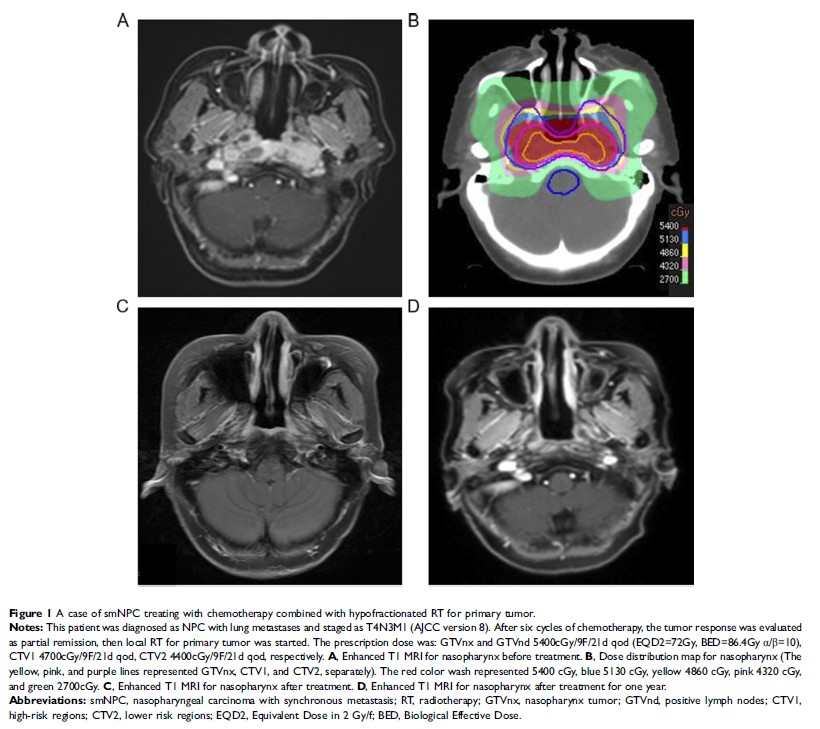

- 作者:赵静,刘晓亮,王伟平,胡克,张福泉,侯晓荣,孟庆宇

- 期刊:Cancer Management and Research